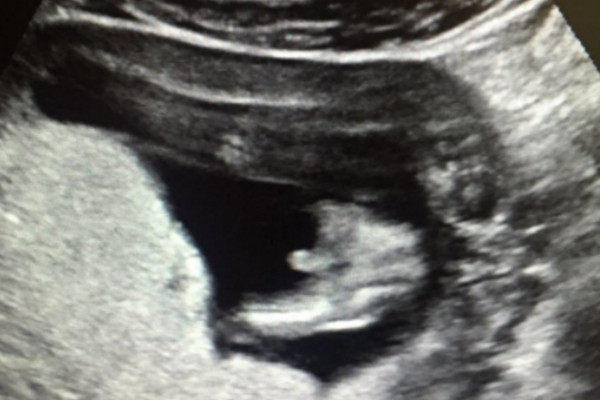

孕期间出现褐色分泌物在妊娠早期需要警惕先兆流产、流产的可能,应及时到医院抽血化验绒毛膜促性腺激素、孕酮水平,以及子宫附件彩超等,了解宫内胎儿生长发育情况有无异常。弯腰、深蹲、跑步等都是一个动作可能立马流产高风险行为,女性在怀孕期间需谨慎。